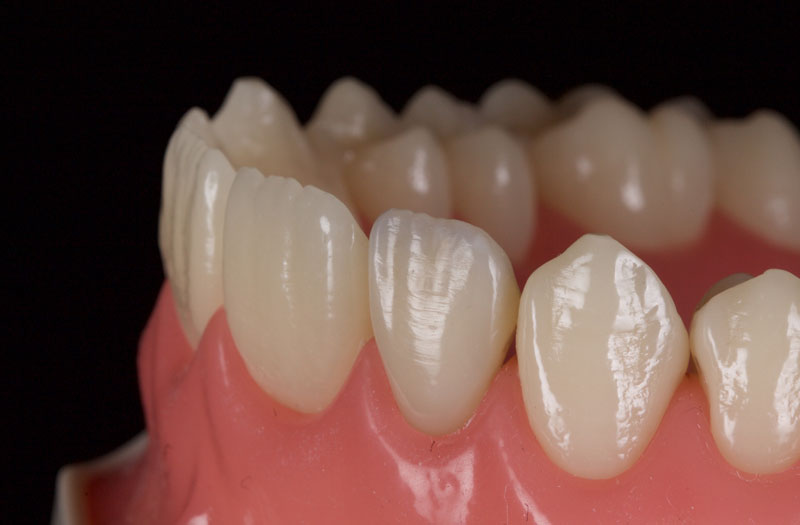

- Single Tooth: This is a microdontia localized to one tooth. Most peg laterals seen in a general dental practice setting will be of this type. See Fig. 3 (pre-op) and Fig. 4 (immediate post-op treated with direct resin).

After a final polish with a felt wheel and aluminum oxide polish (Flexibuff and Enamelise, Cosmedent) at decreasing pressure and increasing speed, the restoration is complete (Figs. 18 and 19.)